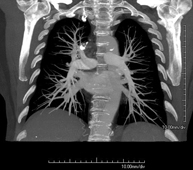

Prueba diagnóstica que consiste en el estudio de la aorta torácica (principal arteria del tórax) mediante el empleo de un equipo de TC (Tomografía Computarizada). Esta técnica requiere el empleo de contraste yodado, y proporciona imágenes de alta definición anatómica. El uso del TCMD (TC Multidetector) acorta el tiempo de exploración, disminuye la dosis de radiación y mejora la calidad de la imagen. Gracias a los múltiples detectores, en determinados estudios se puede acoplar la obtención de la imagen con el latido cardíaco, técnica que permite el estudio de la válvula aórtica y de la raíz de la arteria aorta (primeros centímetros), donde el latido del corazón suele provocar múltiples artefactos de movimiento. - Angio –TC Artèries pulmonars (estudi TEP, Tromboembòlia pulmonar)

Prova diagnòstica que consisteix en l'estudi de les artèries pulmonars mitjançant l'ús d'un equip de TC (Tomografia Computeritzada) per obtenir imatges bi i tridimensionals. En aquest estudi és imprescindible l'ús de contrast iodat que permet una millor definició anatòmica. Aquesta prova està principalment indicada en els casos de sospita de tromboembòlia pulmonar (TEP) per descartar o confirmar la presència de coàguls sanguinis a l'interior de les artèries. - TC Tòrax d'alta resolució

Prova diagnòstica que consisteix en l'estudi de les artèries pulmonars mitjançant l'ús d'un equip de TC (Tomografia Computaritzada) i amb l'obtenció d'imatges bi i tridimensionals. En aquest estudis és imprescindible l'ús de contrast iodat, que permet una millor definició anatòmica. Aquesta prova està principalment indicada en els casos en els quals hi hagi sospita de tromboembolisme pulmonar (TEP) per descartar o confirmar la presència de coàguls sanguinis a l'interior de les artèries. - Angio TC cardíac